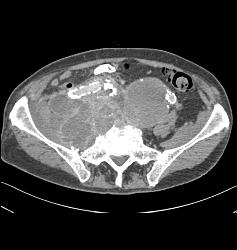

Iliac Artery Aneurysm With Iliopsoas Bleed